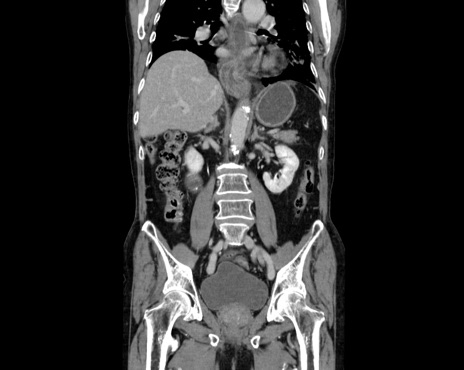

症例26(冠状断像)

【症例】80歳代男性

【主訴】嘔吐

【現病歴】昨晩2回嘔吐あり、今朝になっても嘔吐あり。来院。

【既往歴】胃潰瘍

【身体所見】意識清明、BT 37.6℃、BP 166/95mmHg、HR 100bpm、SpO2 97%、腹部:平坦・軟、腸蠕動音聴取良好、圧痛なし。

【データ】WBC 21900、CRP 1.4